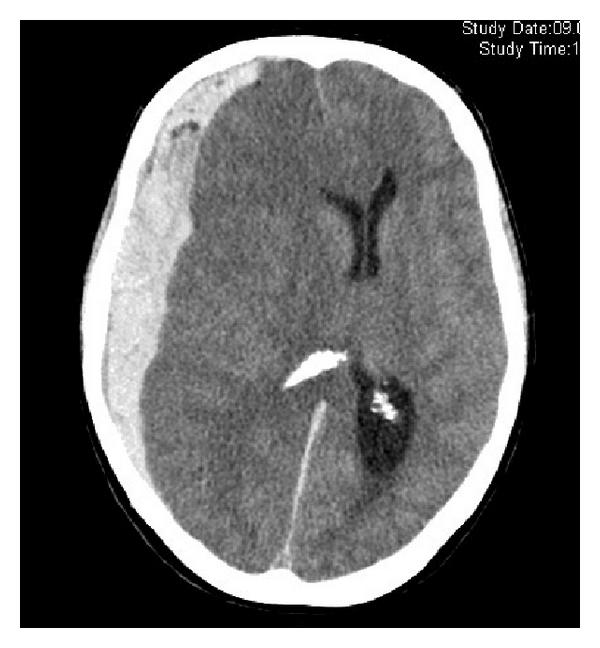

硬腦膜下出血

即血液積聚於硬腦膜與蜘蛛網膜之間,成因多為外傷撞擊,而扯斷了腦膜的血管。患者或突然出現認知障礙、反應遲緩、言語不清、行路不穩。只要打開硬腦膜引流積血便可回復正常,但頭骨或須待腦壓降低後才可放回。